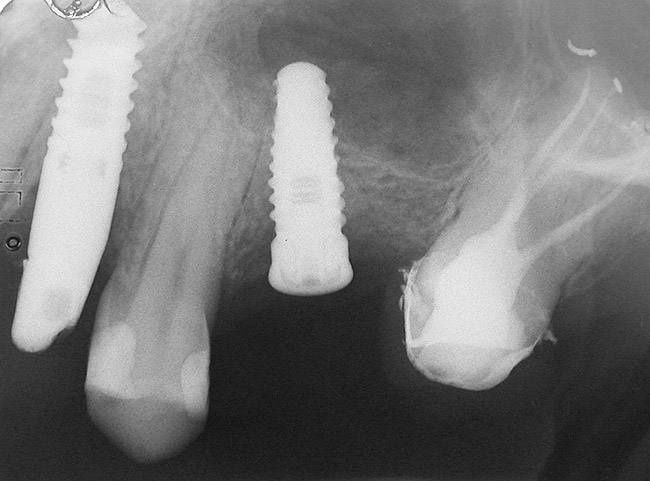

A 55-year-old male was referred for implant placement and prosthetic rehabilitation in the area of tooth No. 15. The tooth had been extracted 4 years prior. The radiograph revealed inadequate bone height for implant positioning (Figure 6). It was decided to insert an implant that was 11.5 mm in length and 3.75 mm in diameter, performing a slight osteotomic maxillary sinus lift. A heterologous bone graft also was planned to obtain a larger sinus lift.

A full-thickness mucoperiosteal flap was raised, and alternating osteotomes were used to prepare the implant site. After achieving a length of 7 mm (Figure 7A and Figure 7B), heterologous bone graft was implanted and the osteotome sequence was repeated. The implant showed primary stability.

Figure 8  At 4 months after treatment, the radiograph revealed the presence of a bone layer surrounding the implant.

Figure 6  Preoperative radiograph of the area around tooth No. 15.

Figure 6

Figure 8